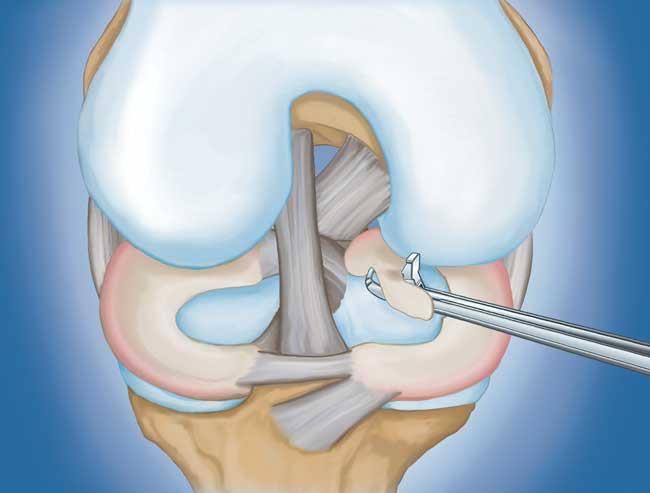

程序。 膝關(guān)節(jié)鏡檢查是最常進(jìn)行的外科手術(shù)之一。在這個(gè)過(guò)程中,外科醫(yī)生通過(guò)膝蓋上的一個(gè)小切口(入口)插入一個(gè)微型相機(jī)。這提供了膝蓋內(nèi)部的清晰視圖。然后外科醫(yī)生通過(guò)兩個(gè)或三個(gè)其他小入口插入手術(shù)器械以修剪或修復(fù)撕裂。

- 部分半月板切除術(shù)。 在這個(gè)過(guò)程中,受損的半月板組織被修剪掉。該程序通常允許在手術(shù)后立即負(fù)重和全方位運(yùn)動(dòng)。

在這段簡(jiǎn)短的手術(shù)視頻中,半月板部分切除術(shù)期間使用電動(dòng)剃須刀平滑了退行性半月板撕裂。

- 半月板修復(fù)。 一些半月板撕裂可以通過(guò)將撕裂的碎片縫合(縫合)在一起來(lái)修復(fù)。撕裂能否成功修復(fù)取決于撕裂的類(lèi)型,以及受傷半月板的整體狀況。因?yàn)榘朐掳灞仨氁黄鹩希迯?fù)的恢復(fù)時(shí)間比半月板切除術(shù)長(zhǎng)。